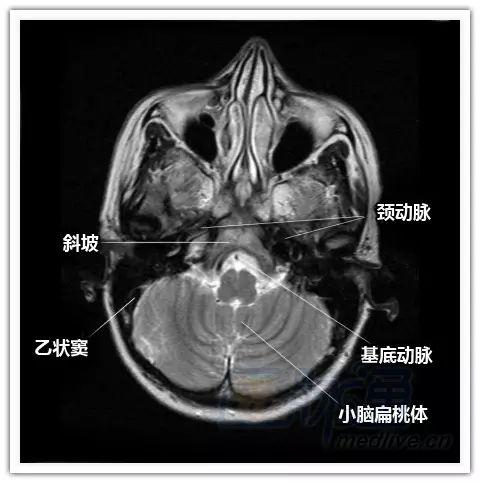

横断位图像:由足侧至头侧